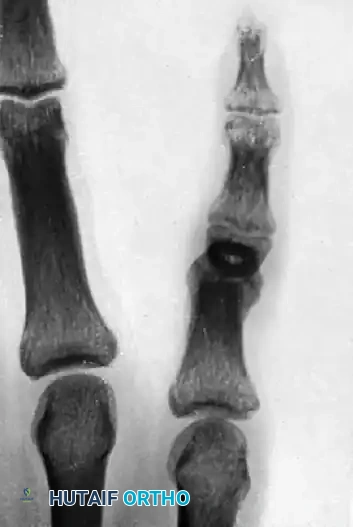

FIGURE 67-73: A, Malunited phalangeal fracture. B, Result is satisfactory after treatment by osteotomy and fixation with a medullary bone peg.